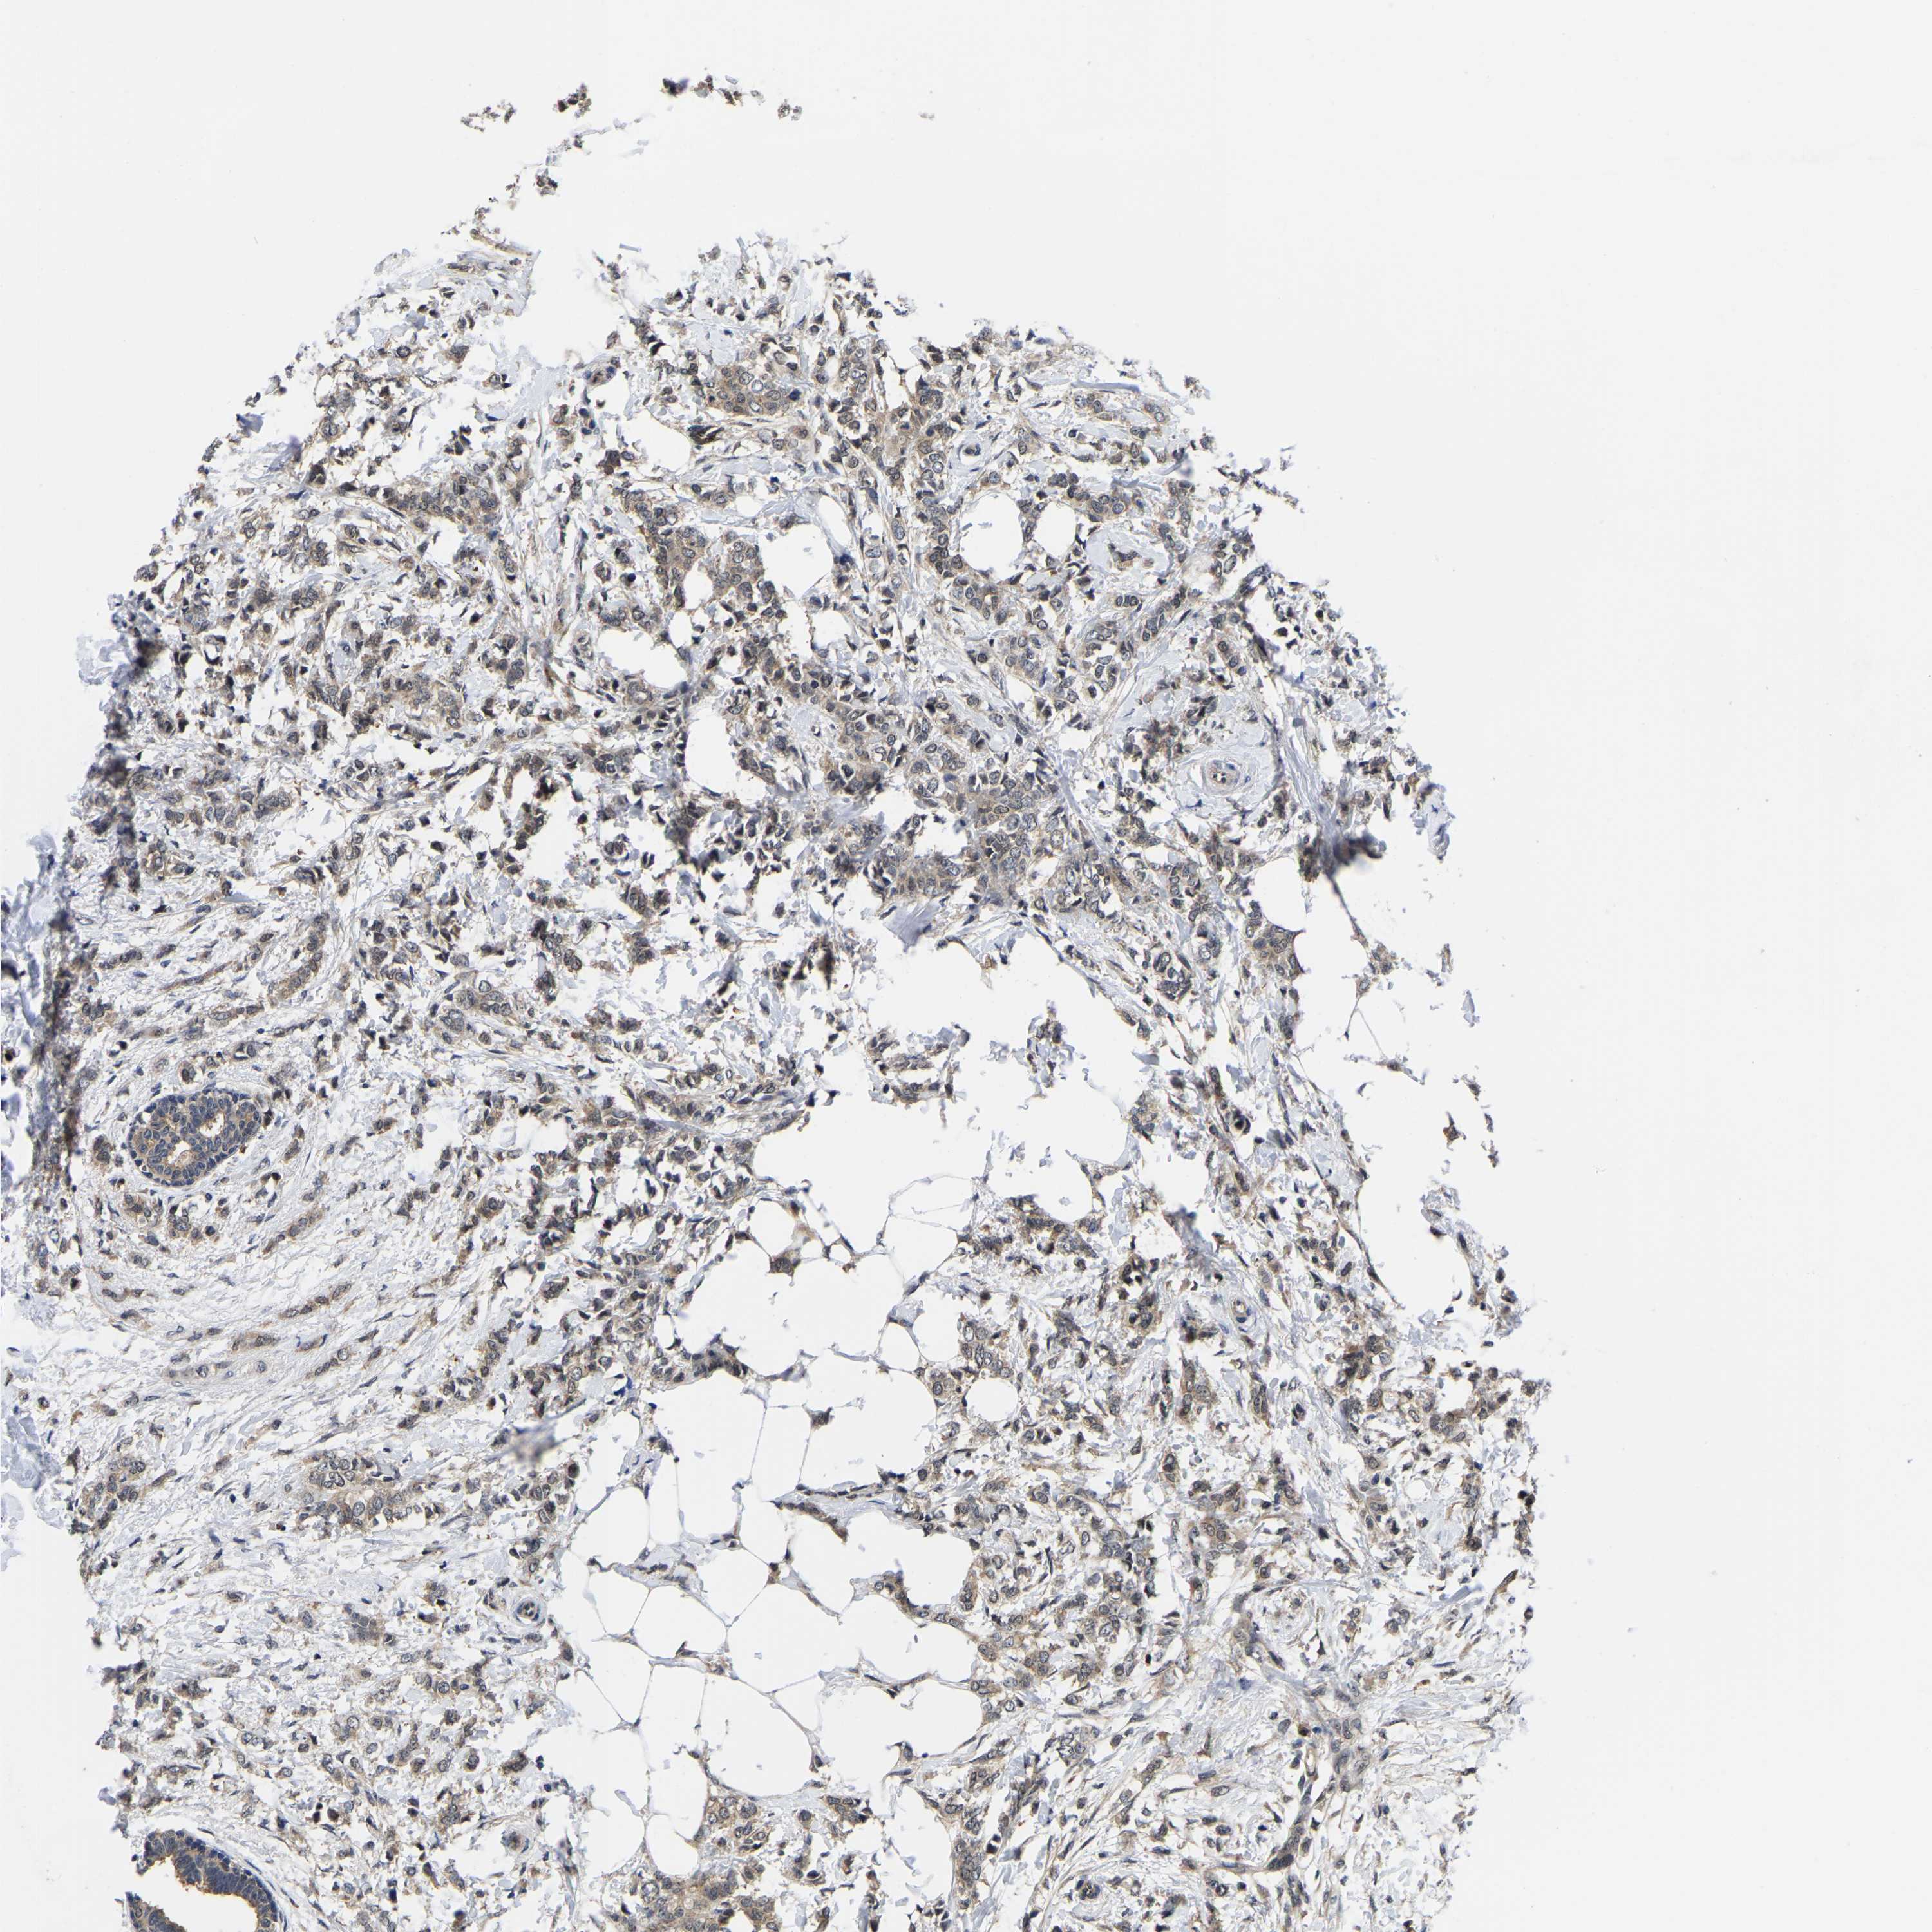

BRCA TCGA BRCA VALIDATION PROTEIN EXPRESSION

ANTIBODIES

AND

VALIDATION